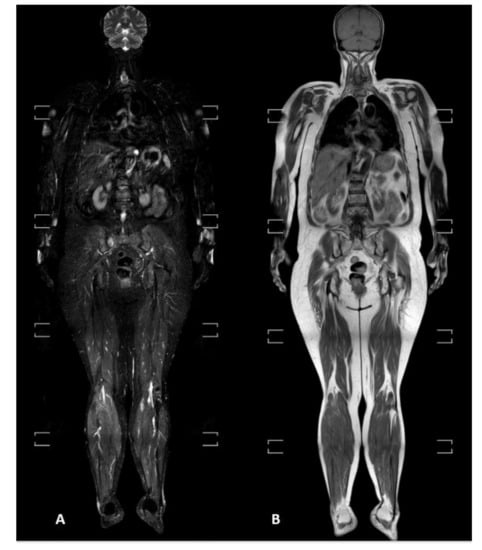

3.3. Radiological Pattern and Lesions’ Distribution

3.4. Standard vs. Short Protocols

2.1. WBMRI Protocol